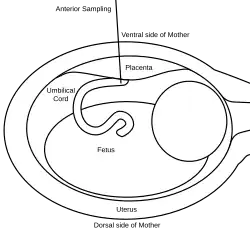

A 20 or 22 gauge spinal needle is typically used in PUBS and may be prepared with an anticoagulant, which helps to reduce the risk of clot formation.[11] During the procedure, the first step is to locate a relatively stable segment of the umbilical cord. A typical sampling site would be where the segment of the umbilical cord is closest to the placenta. However, there is a risk of maternal blood contamination at this site. Blood sampling may be achieved with more ease if the placenta is in the anterior position. However, if the placenta is in the posterior position, the fetus might block direct access to the umbilical cord. Once the umbilical cord is reached and the correct position of the needle is confirmed, the fetal blood is drawn. The needle is removed after all necessary samples are taken. The site of puncture is monitored after the procedure for bleeding. Also, if the fetus is viable, fetal heart rate is monitored post-procedure for one to two hours.[9]